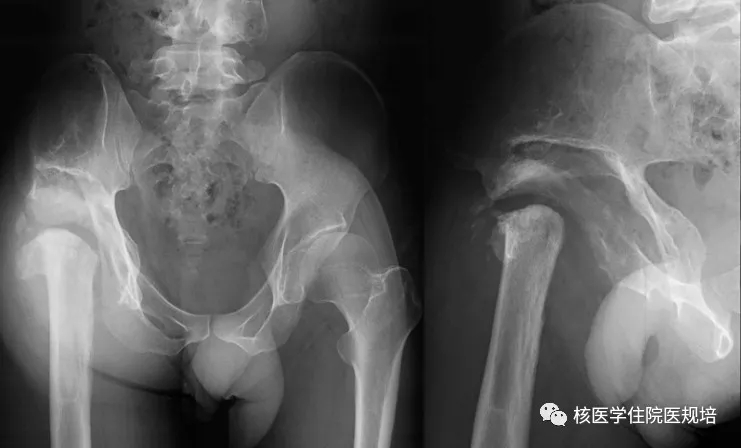

患者男性,30岁, 3个月前无明显诱因突发大小便失禁,同时伴下肢活动障碍,为进一步诊治就诊于我院。既往史:出生后诊断为先天性无痛无汗症,其他无特殊病史。查体:患者轮椅进入病房,神志清楚,对答切题;全身皮肤干燥、见多处瘢痕,皮肤痛觉缺失,指甲发育不良,脊柱生理屈度存在,无明显棘突压痛。双上肢未见明显畸形,肌力、肌张力未见明显异常。左下肢可见膝关节不规则隆起,表面不光滑,质硬,无波动感,关节屈伸正常,局部皮温正常,无皮肤红肿、破溃或静脉怒张,压痛(-);右下肢未见明显异常。双下肢感觉较弱,巴氏征(-)。实验室检查无明显异常发现。腰椎X光片及CT(图1.2)检查发现腰椎退行性变,L3、L4椎体融合,骨小梁结构模糊,L5/S1椎间盘膨出,前纵韧带钙化;多关节部位X光片示右髋关节(图3)髋臼扩大、骨质吸收,股骨头脱位,骨骺未融合,残端如刀削状,关节肿胀,内见多发碎骨片;左膝关节(图4)正常关节结构消失,关节对位差,骨端膨大,周围见多发游离骨块,股骨下段、胫骨平台见骨质破坏,关节周围软组织肿胀;右踝关节(图5)诸骨在位,胫腓骨远端膨大变形,距骨变扁,诸骨骨质密度弥漫减低,骨小梁稀疏,内外踝边缘可见骨质增生;关节间隙狭窄。为进一步了解全身骨病变情况行99mTc-MDP全身骨显像(图6)。

图1.

图2.